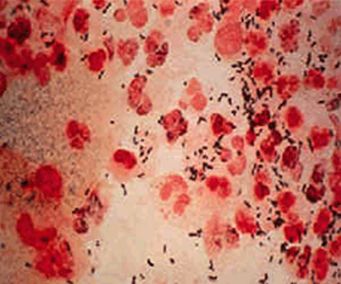

淋病是淋病奈瑟菌(简称淋球菌)引起的以泌尿生殖系统化脓性感染为主要表现的性传播疾病。其发病率居我国性传播疾病第二位。淋球菌为革兰阴性双球菌,离开人体不易生存,一般消毒剂容易将其杀灭。那么产生淋病的原因有哪几种,下面我们请北京京城皮肤医院的专家给大家讲解一下。